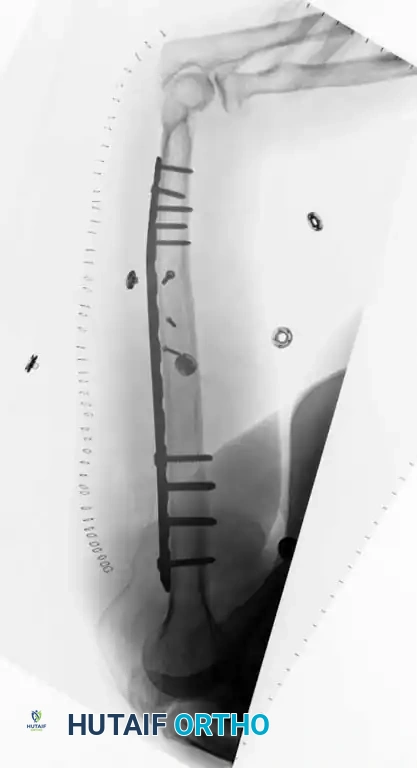

For fractures located at the distal metaphyseal-diaphyseal transition zone, standard straight plates may not provide adequate distal purchase. In these scenarios, dual 3.5-mm LC-DCPs or anatomically pre-contoured extra-articular distal humerus plates are required.

Fig. 54-29 Dual plating of distal metaphyseal-diaphyseal humeral shaft fracture.

Fig. 54-31 A, Segmental shaft fracture with extension into proximal humerus. B and C, Long plate used to obtain secure fixation.

Biomechanical Principle: Generally, a minimum of eight cortices (four bicortical screws) above and below the fracture are necessary to prevent screw pullout. In osteoporotic bone, longer plates spanning a greater working length, locking screws, or methylmethacrylate augmentation may be required.